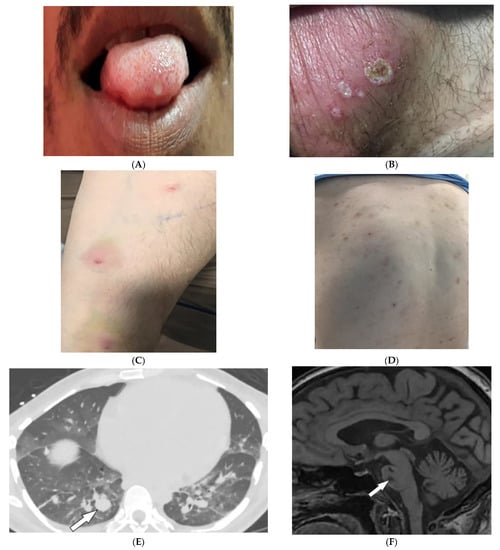

3.9. Fong Disease

| Fong (Nail–patella) syndrome | Hypoplastic nails, triangular lunulae Hypoplastic patellae Focal segmental glomerulosclerosisLester iris | Bilateral absence of patellae Posterior iliac horns (Fong’s prongs) Subluxation of radial heads |